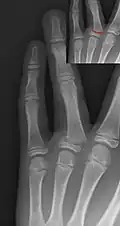

Salter–Harris II fracture of ring finger proximal phalanx. -

Salter–Harris III fracture of big toe proximal phalanx. -